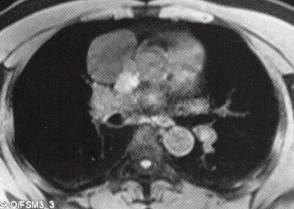

E.H.MRI平扫示肿块位于心底呈长T1、长T2信号,冠状位示肿块呈哑铃状,与心包关系密切

4.MRI表现:可清晰显示囊肿的形态及性质,囊壁在T1WI和T2WI上均呈线样低信号影,囊液呈典型水样长T1、长T2信号,多方位显亦囊肿与心包关系密切。

3.囊性肿块位于心底呈长T1、长T2信号,冠状位显示肿块呈哑铃状,与心包关系密切。